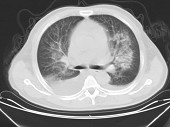

- 单项选择题男,32岁, CT图像如图,最可能的诊断为 ( )

A、肺水肿并双侧胸腔积液

B、周围型肺癌

C、肺动静脉瘘

D、肺错构瘤

E、炎性假瘤